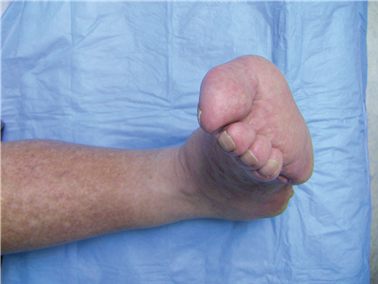

Clinical & Radiographic Imaging Archive